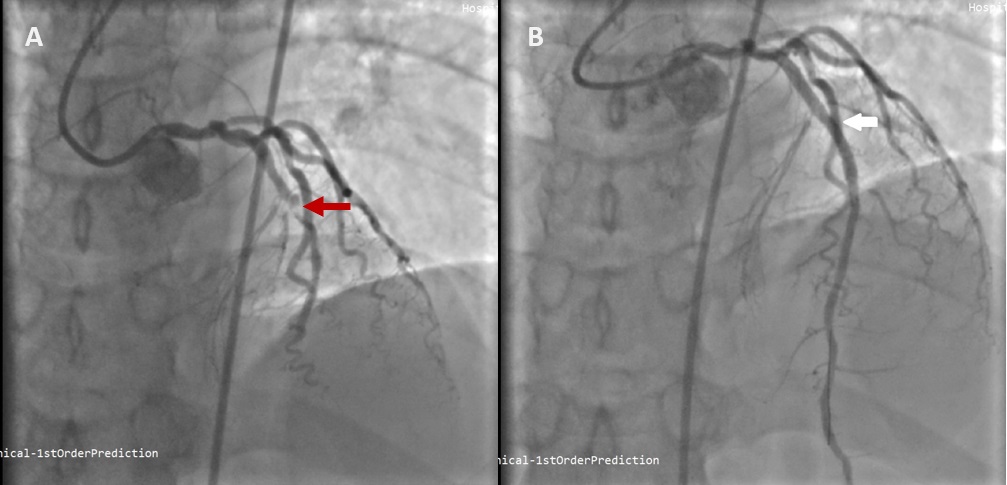

De Winter syndrome is a rare but important ST-elevation myocardial infarction (STEMI) equivalent, that is characterised by severe stenosis of the left anterior descending artery (LAD). It can be easily misdiagnosed due to its atypical electrocardiogram (ECG) pattern which causing a delay in reperfusion, hence increases risk of mortality. Herein, we reported a 38-year-old man presented to the emergency department (ED) with initial ECG showed hyperacute T wave, which later evolved to de Winter syndrome ECG pattern after serial ECG were done. He was immediately referred to the cardiology team and underwent immediate percutaneous coronary intervention (PCI) to revascularise the stenosis found at the left anterior descending artery (LAD). He showed good outcomes and no complication after the procedure. This paper aimed to shed light on the importance of early identification, right diagnosis and treatment in De Winter syndrome case to avoid complications.